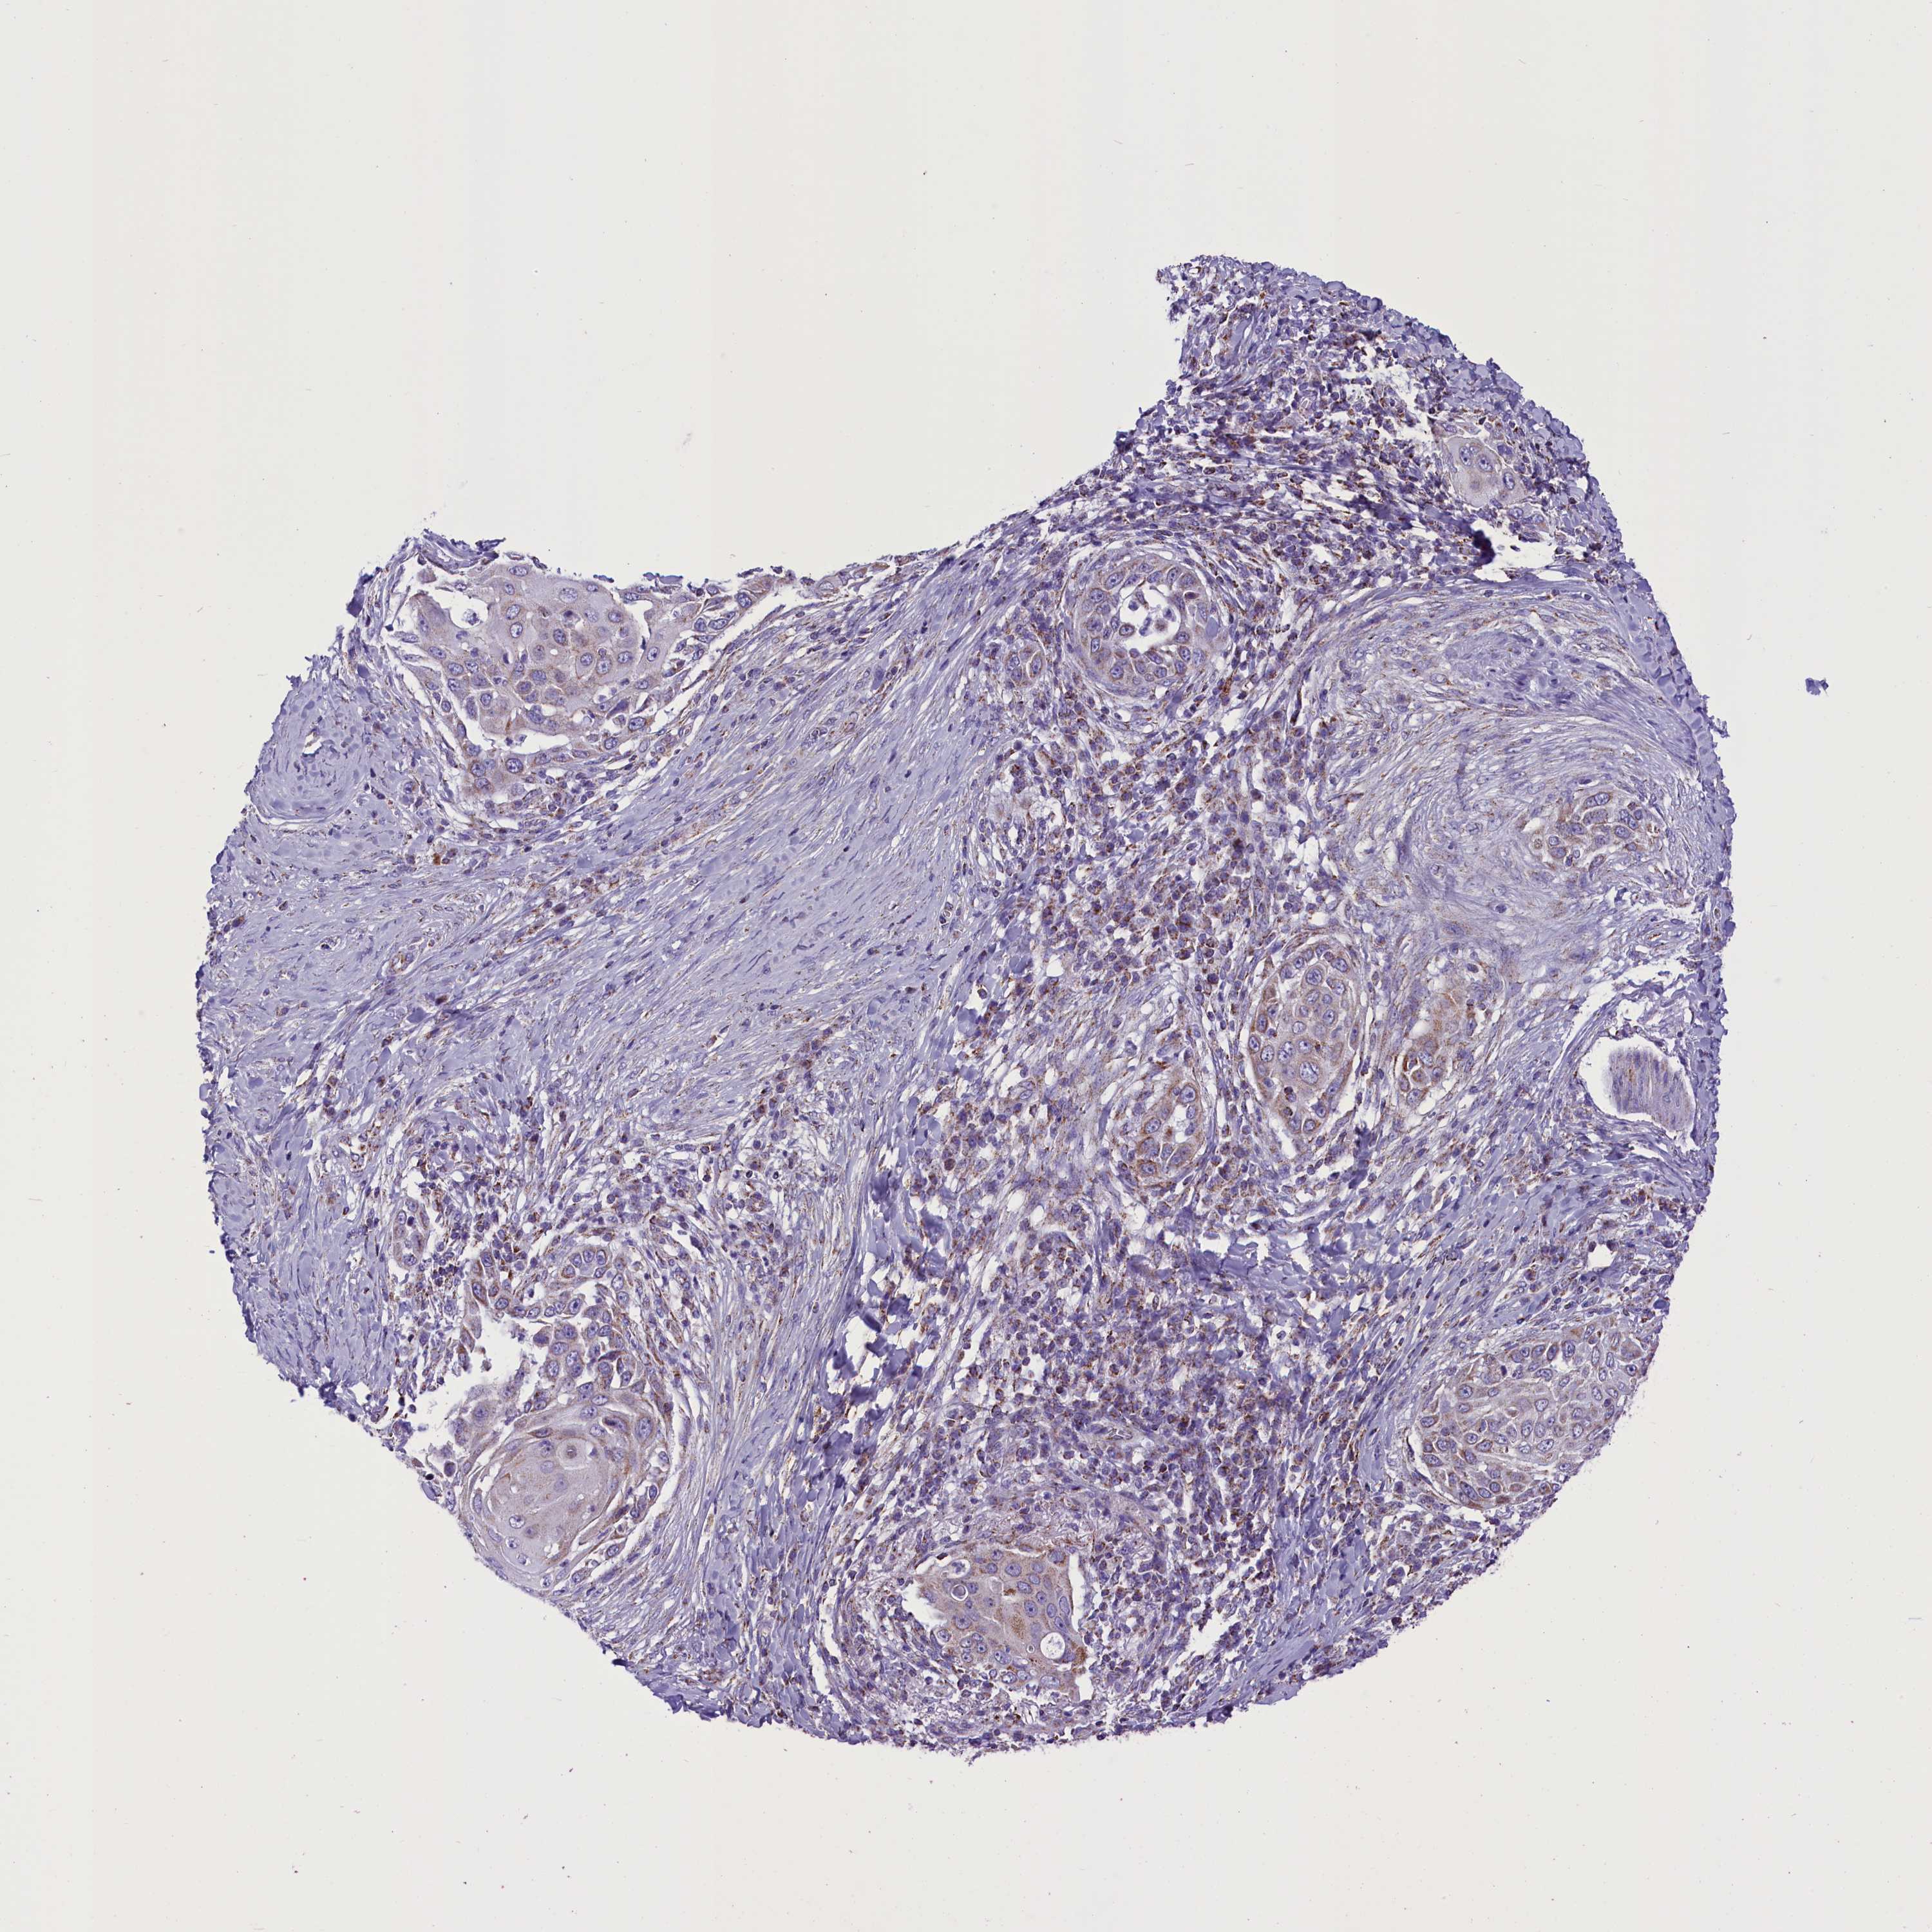

SKIN CANCER - Protein expressioni

A mouse-over function shows sample information and annotation data. Click on an image to view it in a full screen mode. Samples can be filtered based on level of antibody staining by selecting one or several of the following categories: high, medium, low and not detected. The assay and annotation is described here.

Antibody stainingi

Antibody staining in the annotated cell types in the current human tissue is reported as not detected, low, medium, or high, based on conventional immunohistochemistry profiling in selected tissues. This score is based on the combination of the staining intensity and fraction of stained cells.

Each image is clickable and will lead to virtual microscopy that enables deeper exploration of all samples and also displays staining intensity scores, fraction scores and subcellular localization as well as patient and tissue information for each sample.

Antibody HPA042507

Staining

High

Medium

Low

Not detected

Intensity

Strong

Moderate

Weak

Negative

Quantity

>75%

75%-25%

<25%

None

Location

Nuclear

Cytoplasmic/membranous

Cytoplasmic/membranous,nuclear

Squamous cell carcinoma, NOS